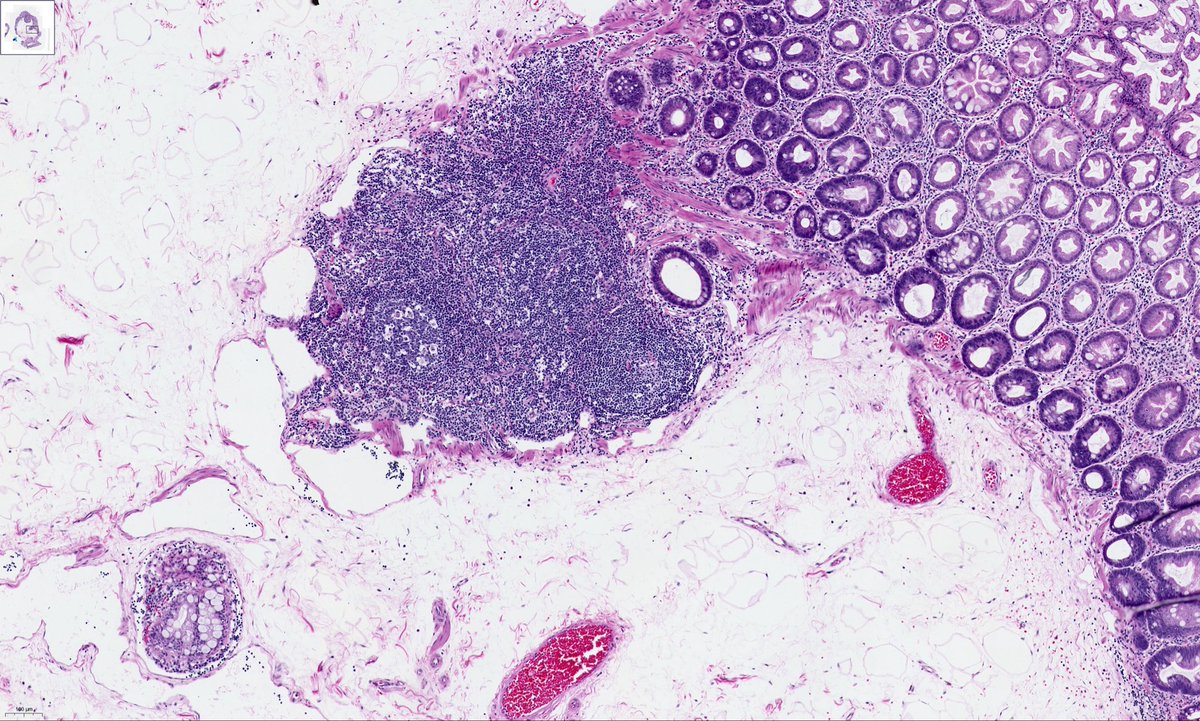

Incidental polyp in the terminal ileum of a colon cancer right hemicolectomy. IHC negative apart from patchy CD34. This is a benign calcifying fibrous tumour. Can be found anywhere in the GI tract and do not have any syndromic associations (IgG4 IHC was less than 40%) #GIpath